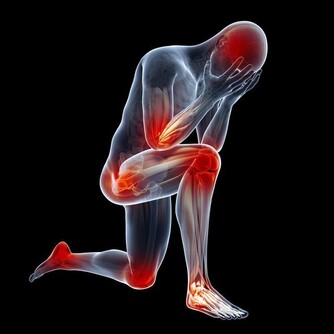

猝死都有那些徵兆呢?來看一下第一個:出現胸悶、呼吸急促的現象

如果在經過大量激烈的運動後,感到胸悶、呼吸急促或者難以呼吸的情況時,這個時候很可能就是你的心臟給你的身體發出的預警。所以出現這種情況,最好即時到醫院檢查一下身體,如果不加以重視的話,多次出現這種情況,很可能會發生猝死。

第二個:出現暈倒

暈倒其實是猝死的最大一種徵兆。其實發生暈厥這種現象,很大程度上都是因為心率減慢或者停止,一旦心率減慢的話,大腦就會產生供血不足,供血不足導致的一個後果就是缺氧,從而就會發生暈倒的現象。所以如果出現暈厥的症狀,要及時檢查,不能放任不管。也許下次就會發生猝死。